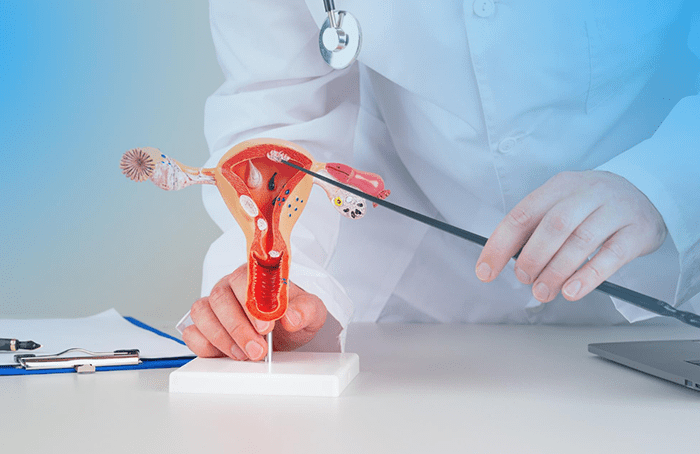

Síndrome de Ovario Poliquístico

Tratamiento multidisciplinario para manejar los síntomas del SOP y mejorar la calidad de vida mediante la regulación hormonal y reproductiva.

Después de años luchando con síndrome de ovario poliquístico, finalmente encontré a alguien que entendió mi situación. La Dra. Clavijo no solo trató mis síntomas, sino que también me ayudó a entender mi condición.